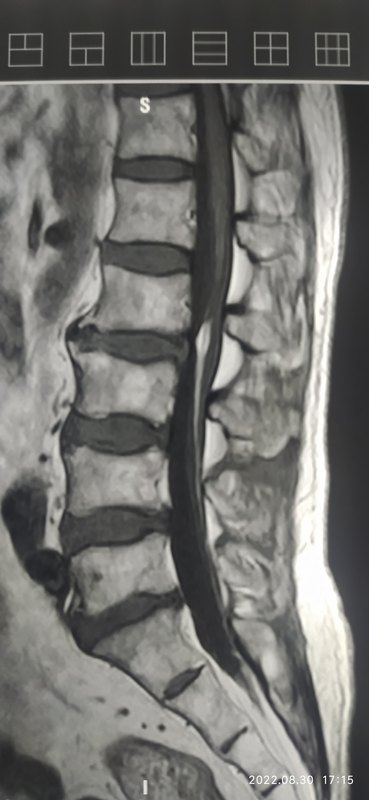

終絲纖維脂肪瘤

???終絲纖維脂肪瘤(fibrolipomaofthefilumterminale),又稱終絲纖維脂肪浸潤,是指含脂肪的直徑超過2mm的終絲,是椎管內(nèi)脂肪瘤的一種。國外報道發(fā)病率0.24%-6%。終絲脂肪瘤發(fā)病原因尚不十分明確,有文獻報道可能與神經(jīng)系統(tǒng)發(fā)育過程中中胚層細胞移行異常有關。???如果沒有脊髓栓系等神經(jīng)癥狀,可認為是一種正常變異。???終絲脂肪瘤可累及硬膜下終絲或硬膜外終絲,也可全層受累。???位于硬膜下的終絲脂肪瘤多呈紡錘形,向下至終絲穿過硬模處逐漸變細,最多見于腰骶部,可合并其他畸形,以神經(jīng)管閉合不全最多見,如脊柱裂、脊膜膨出等。影像學表現(xiàn)??椎管內(nèi)沿終絲走行區(qū)線樣T1、T2高信號影,抑脂序列高信號消失。??軸位T2典型的化學移位征象,即椎管內(nèi)脂肪瘤的周圍可見沿頻率編碼方向的新月形低信號影,周邊包繞橢圓形等或略高信號邊,稱為“化學位移黑白邊偽影”。??同時在腦脊液與硬膜外脂肪囊之間可見自左向右與脂肪瘤表現(xiàn)相反的包繞硬膜的小新月形高信號和低信號。